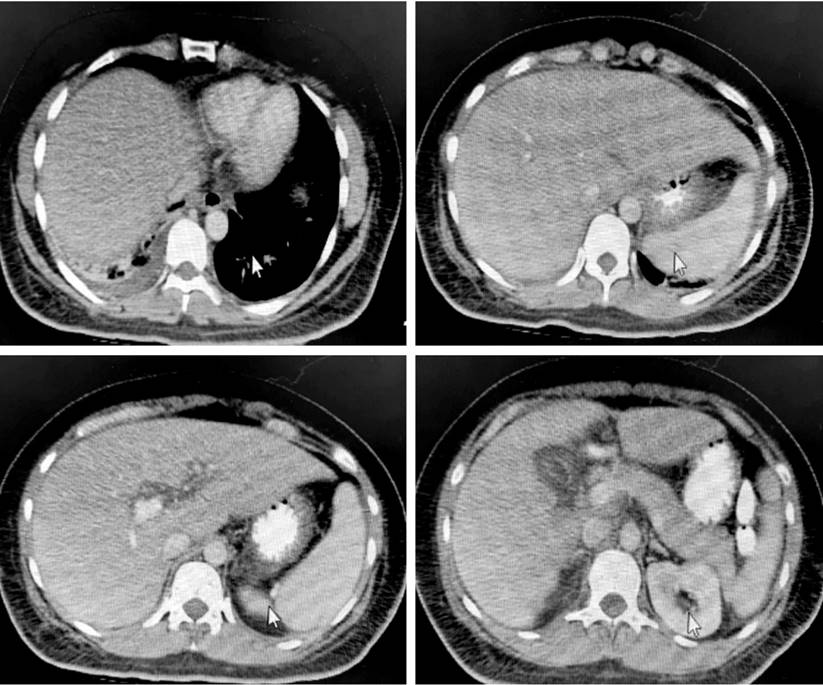

Figura 1 Tomografía axial computarizada (TAC) de abdomen de la paciente. Derrame pleural laminar derecho con atelectasias subsegmentarias. Esteatosis hepática difusa sin lesiones focales. Hallazgos descritos a nivel pancreático que sugieren proceso edematoso intersticial Balthazar C. Índice de gravedad 2. Imagen nodular hipodensa renal derecha compatible con quiste. Liquido laminar intraabdominal. Cortesía del departamento de radiología HUDN.